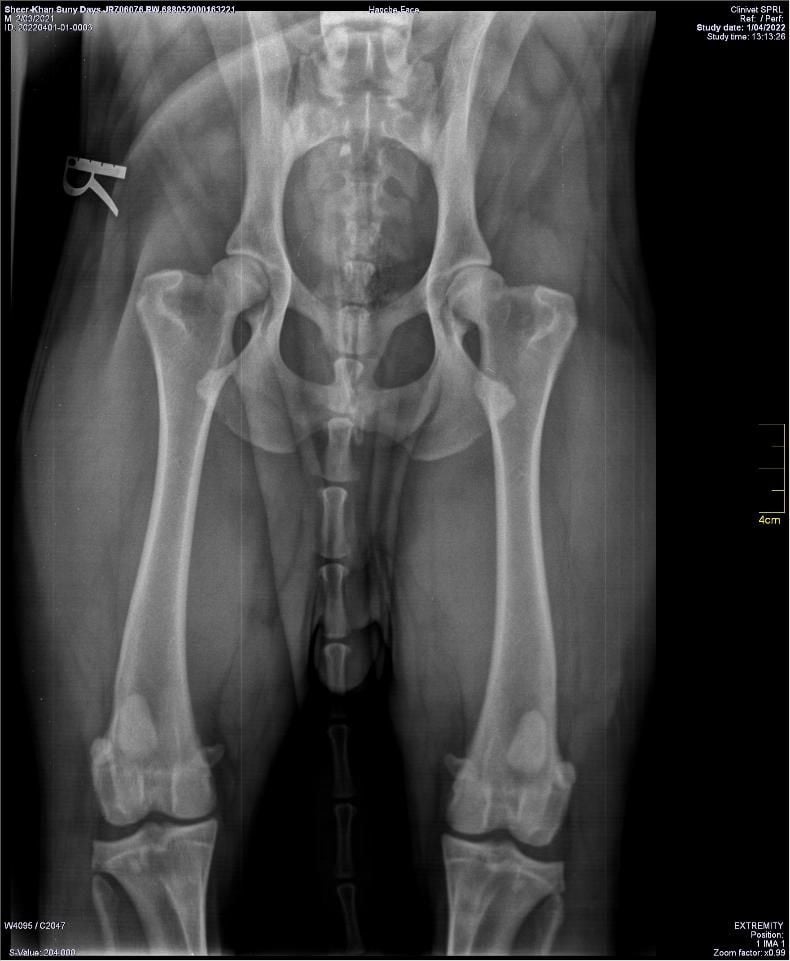

HANCHES

Lecture officielle hanches